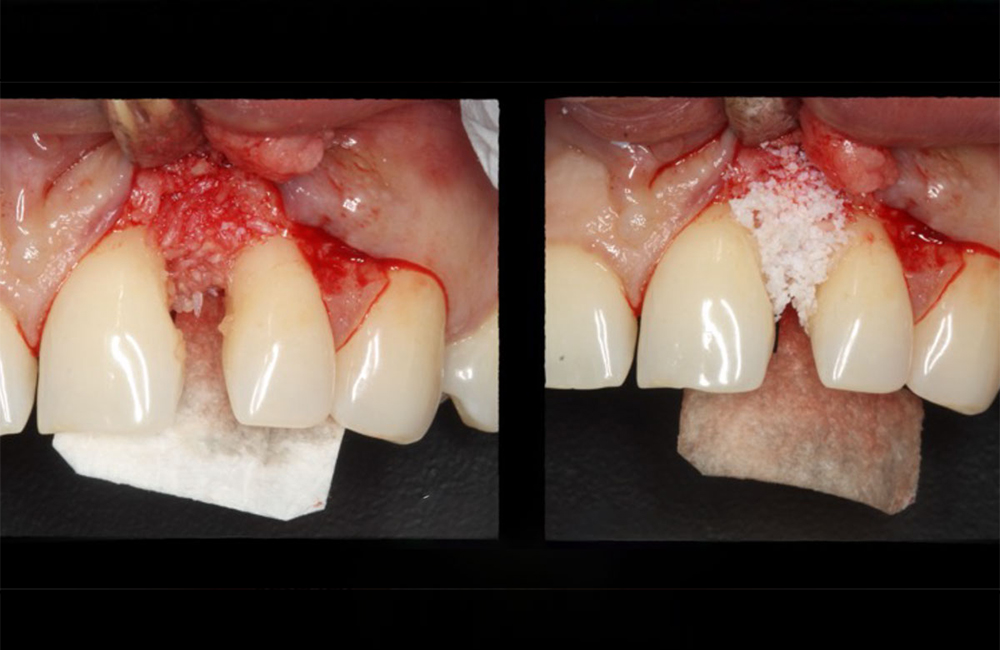

در تکنیک GTR، پودر استخوان معمولاً بهعنوان فیلر (Filler) یا اسکافولد (Scaffold) در زیر غشا قرار میگیرد. نقشهای اصلی آن عبارتاند از:

حفظ فضا (Space Maintenance):

یکی از چالشهای GTR جلوگیری از فروپاشی غشا و تماس آن با بافت نرم است. پودر استخوان با پر کردن حفره، ساختار سهبعدی مورد نیاز برای حفظ فضا را فراهم میکند.القا و هدایت رشد استخوانی:

در حضور پودر استخوان، سلولهای استئوبلاست روی سطح ذرات مینشینند و ماتریکس استخوانی جدید تولید میکنند. برخی انواع پودر، مانند DFDBA، حاوی پروتئینهای القاکننده استخوان (BMPs) هستند که تمایز سلولی را تحریک میکند.افزایش ثبات مکانیکی در ناحیه جراحی:

پودر استخوان با پر کردن نقص استخوانی، از جابهجایی غشا و فروپاشی ساختار بازسازیشده جلوگیری میکند.افزایش حجم استخوان در نواحی تحلیلرفته: